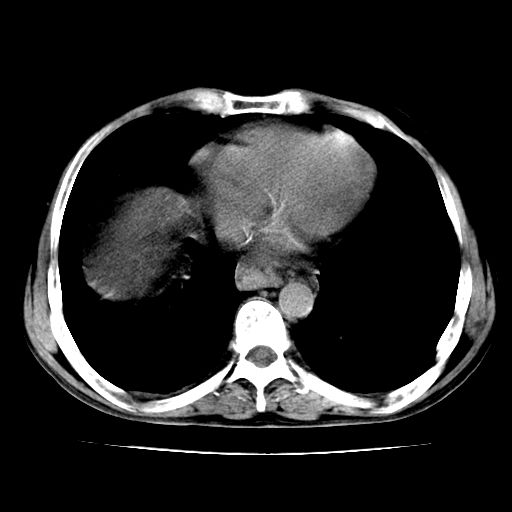

男,55岁,发现“肝硬化”5年,现腰疼、腹胀10余日,巩膜黄染、腹稍胀,肝肋下3指,质硬无压疼,移动性+,血生化:总胆、直胆、间胆均升高。

g1:肝硬化、脾大、腹水。

2:脂肪肝。

3:弥漫性肝癌待排。

肝硬化,脾大,腹水

脂肪肝

肝内多发低密度灶(建议增强扫描除外肝癌)

肝脾肿大,脂肪肝,腹水。建议增强除外肝癌。